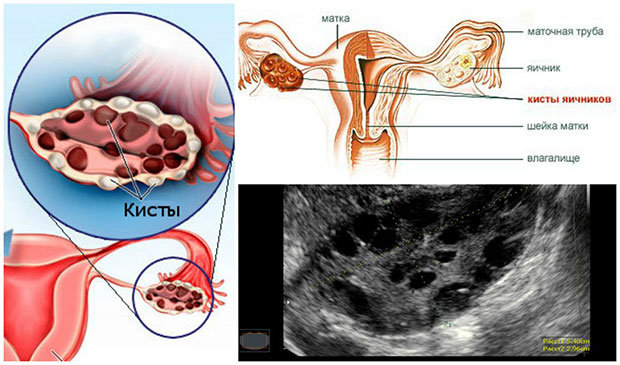

Здравствуйте, дорогие друзья! Основное предназначение женщины – быть мамой. И если одни вовсю им наслаждаются, то другие, в силу различных причин, до сих пор об этом только мечтают. Чаще всего случается так вследствие развития у женщины всевозможных заболеваний, одним из которых и является поликистоз яичников. Симптомы и причины этого явления, а также безопасные методы лечения, мы и обсудим в сегодняшней статье, подробно остановившись на том, возможно ли все же испытать радость материнства с таким диагнозом. Предшествует ему, как правило, нейрообменный сбой, а также нарушение синтеза эстрогенов и андрогенов, в результате которого на поверхности яичников и возникают многочисленные кисты (на фото). В этом случае яйцеклетка уже неспособна выйти из фолликула. Стоит ли говорить о том, что о беременности здесь и речи быть не может.1. Что такое поликистоз яичников

При диагностике в расчет берутся данные лабораторных тестов и УЗИ. При этом существует три признака недуга, но окончательный диагноз ставится даже на основании двух.

- собственно самих кистах на поверхности яичника.

Почему нельзя диагностировать синдром поликистозных яичников на основании одного УЗИ? Дело в том, что узист может ошибиться и принять обычные физиологические изменения в фолликулах за кисты. Тем не менее, если наблюдается увеличение яичников, подкрепляющееся четким сосудистым рисунком, ошибки, скорее всего, быть не может. Хотя точку в исследованиях все равно ставят биохимические тесты.